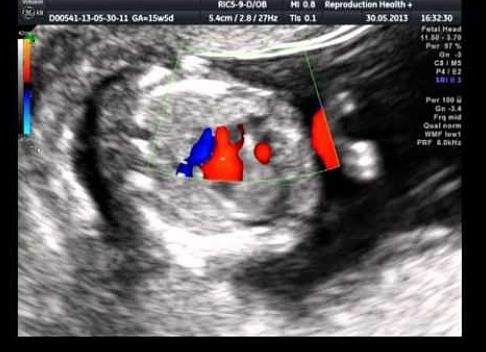

Первое сердцебиение плода на УЗИ

Только женские сердца невозможно обмануть: мамочки инстинктивно чувствуют, что вновь приобретенный тест покажет долгожданные две полоски. Если задержка составляет больше недели, то настало время прояснить ситуацию и определить наличие развивающегося ребеночка в животе у мамочки.